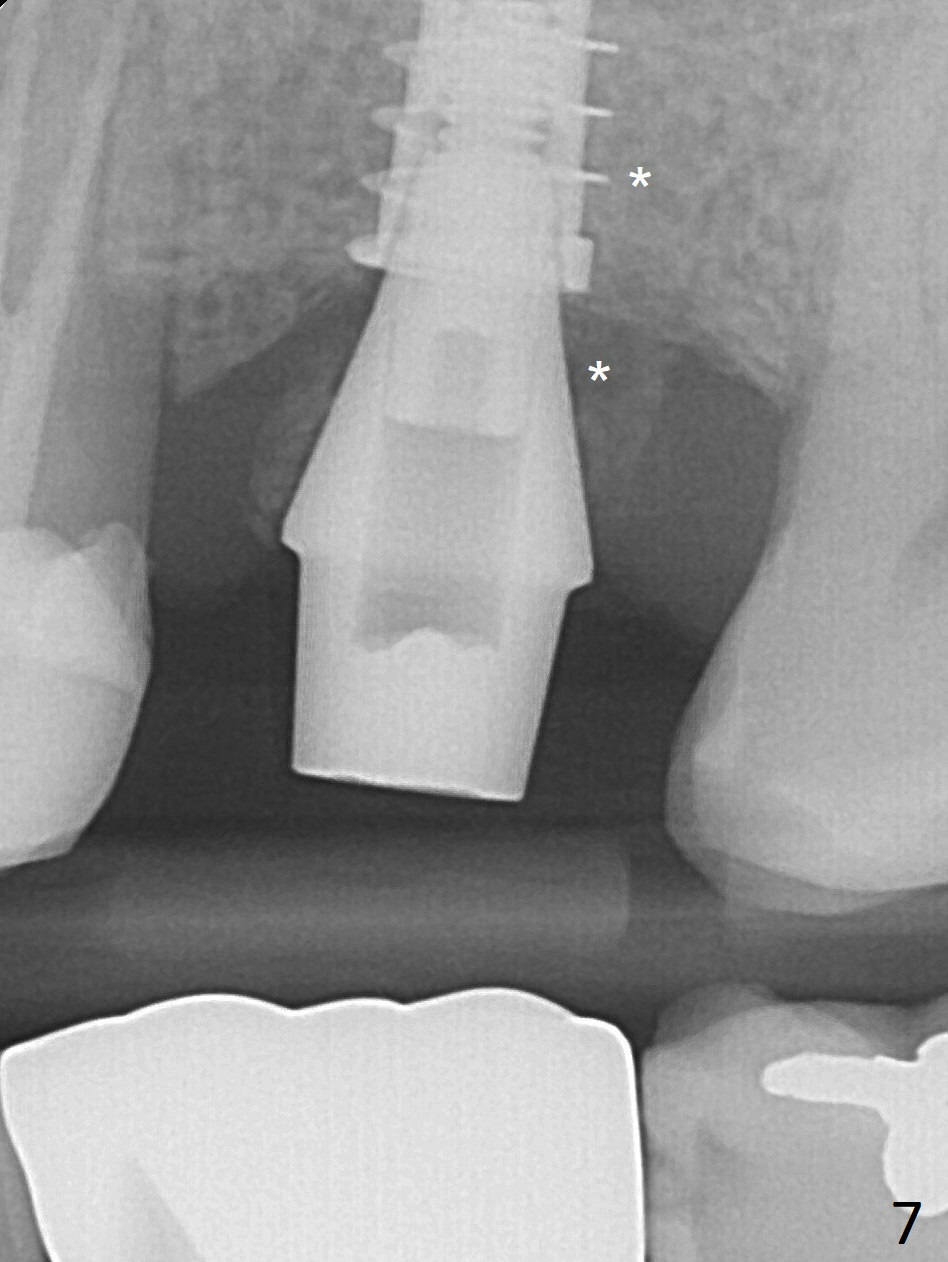

Osteogen plug and allograft (Fig.7 *) are inserted into the remaining distobuccal socket (reduced after bone expansion). The distal socket appears to heal while the bone graft remains at the crest 5 months postop (Fig.11). When #30 develops buccal abscess, the patient masticates on the left, leading to loss of composite at #13 (Fig.14); in fact the abutment at #14 is incompletely seated.